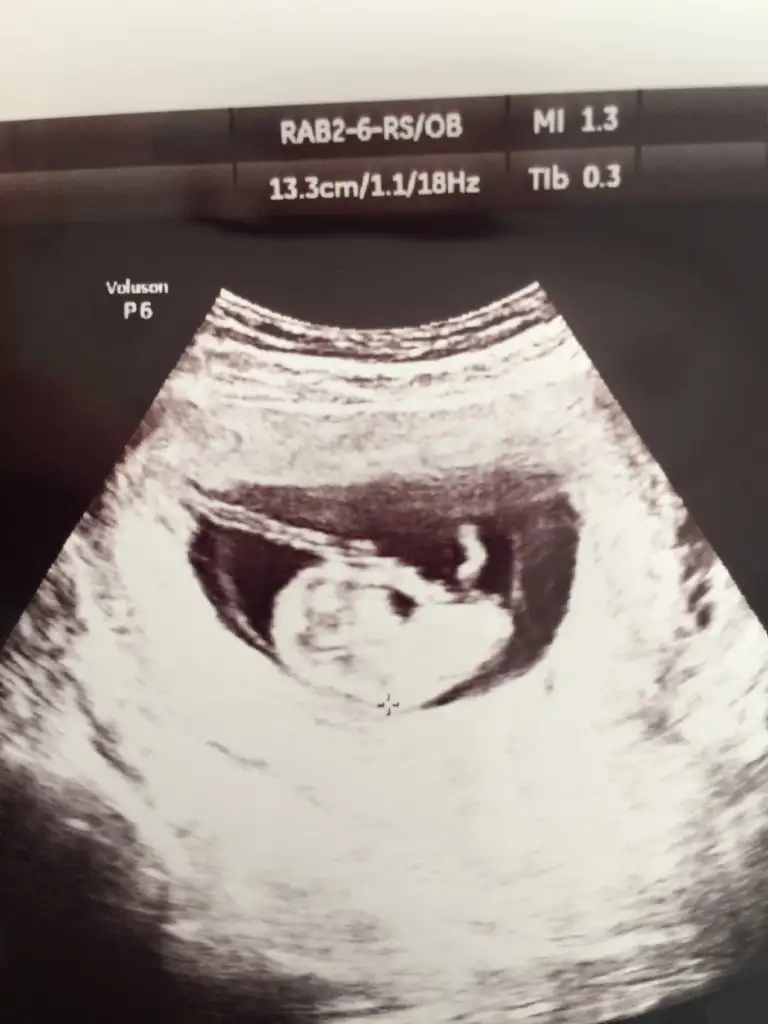

10+1 haftaya göre erkek 11 yada 12 hafta usg tekrar paylaşın çünki 10 haftalarda nub iki tarafa benzerBana da tahmin de buluabilir misiniz?daha küçük ama

Teşekkür ederim yorumladığınız için10+1 haftaya göre erkek 11 yada 12 hafta usg tekrar paylaşın çünki 10 haftalarda nub iki tarafa benzer

10+3 canımKaç haftalık

Erkek diyorum kafa yapısına göre10+3 canım

Erkek gibi geldi banaBenim bebişim bu ultrasonda 11+2 ikinci çocuğum ama bu cinsiyet işinden hiç anlamıyorum. acaba tahmin yapabilir misiniz?

Erkek gibi Canım sağlıkla gelsinmerhaba bugün kontrolüm vardı..